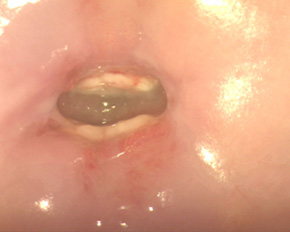

Лікування ерозії шийки матки: пацієнт А